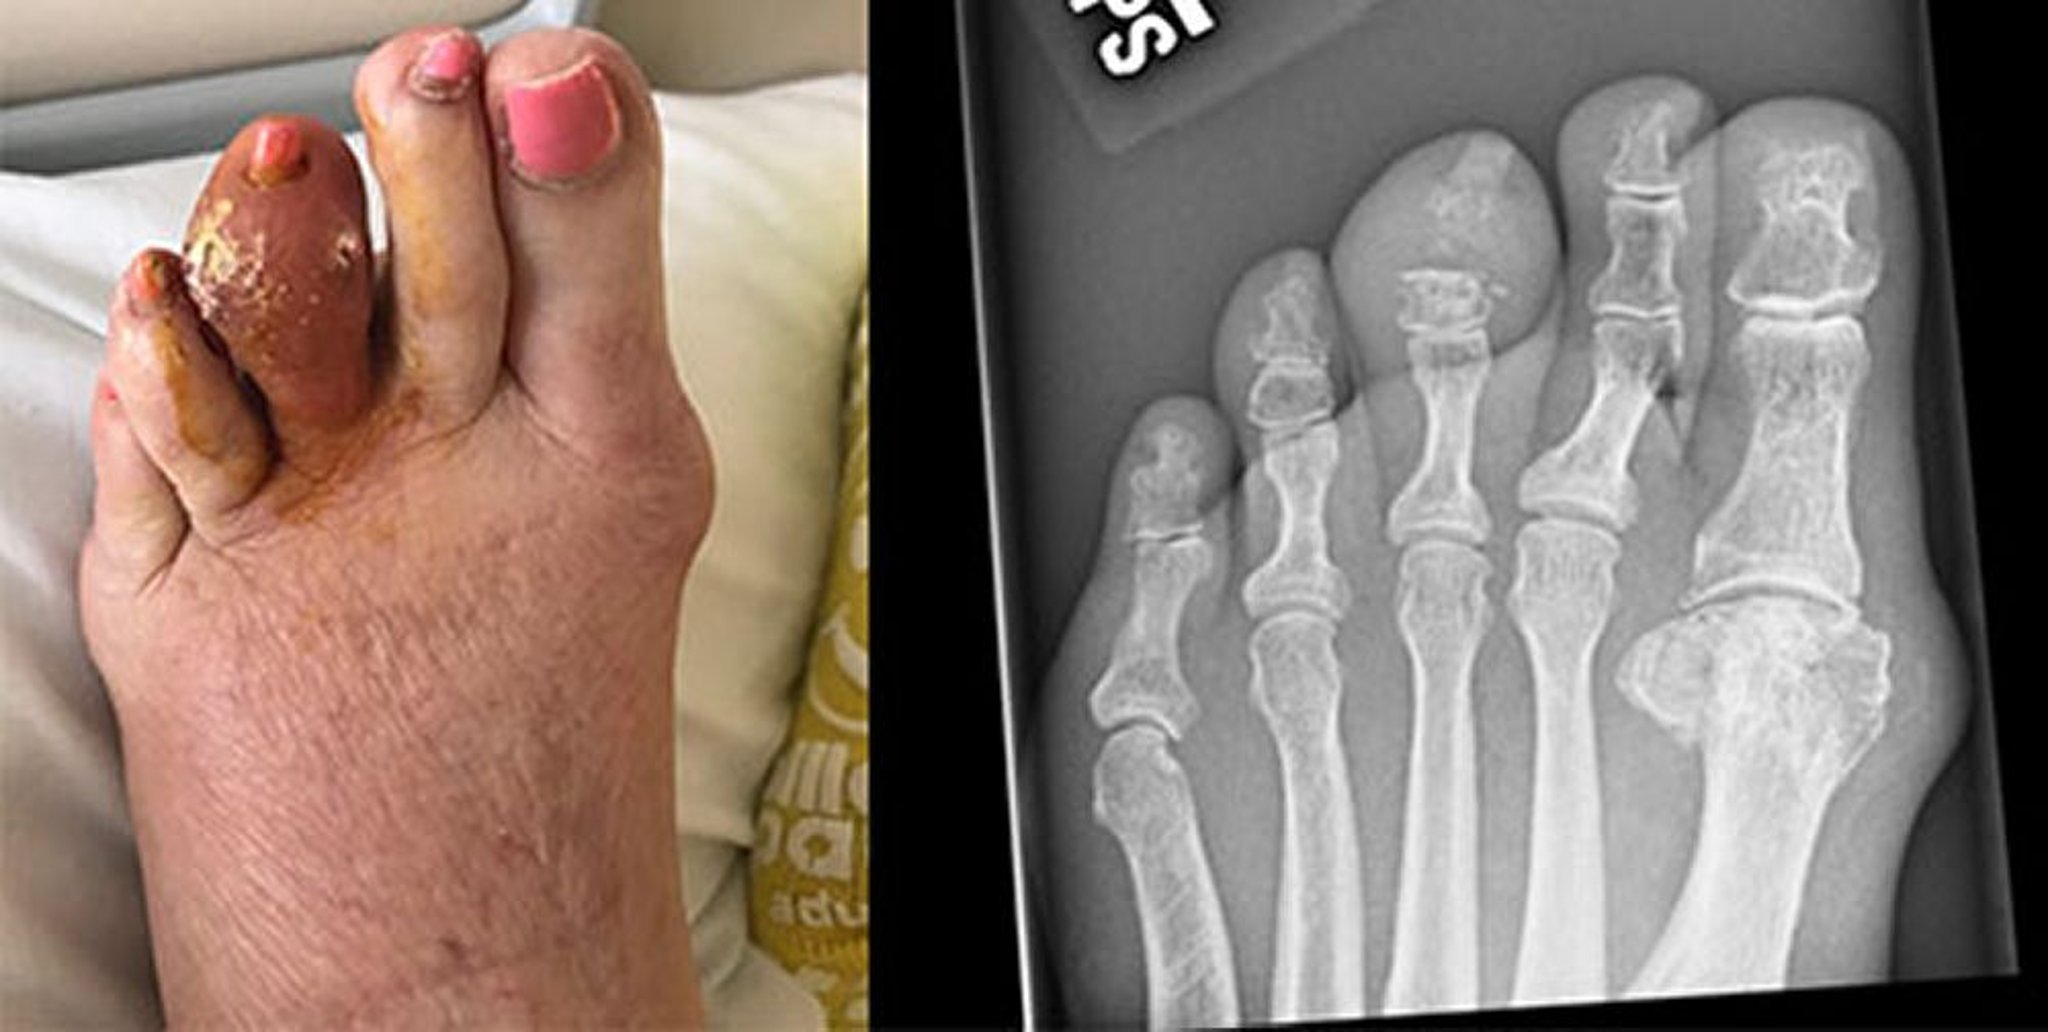

Gota del dedo medio del pie

Esta fotografía muestra un gran tofo en el tercer dedo del pie izquierdo, que se ha fragmentado y liberado ácido úrico endurecido. La radiografía de la derecha muestra la erosión de la falange media y la articulación interfalángica distal.